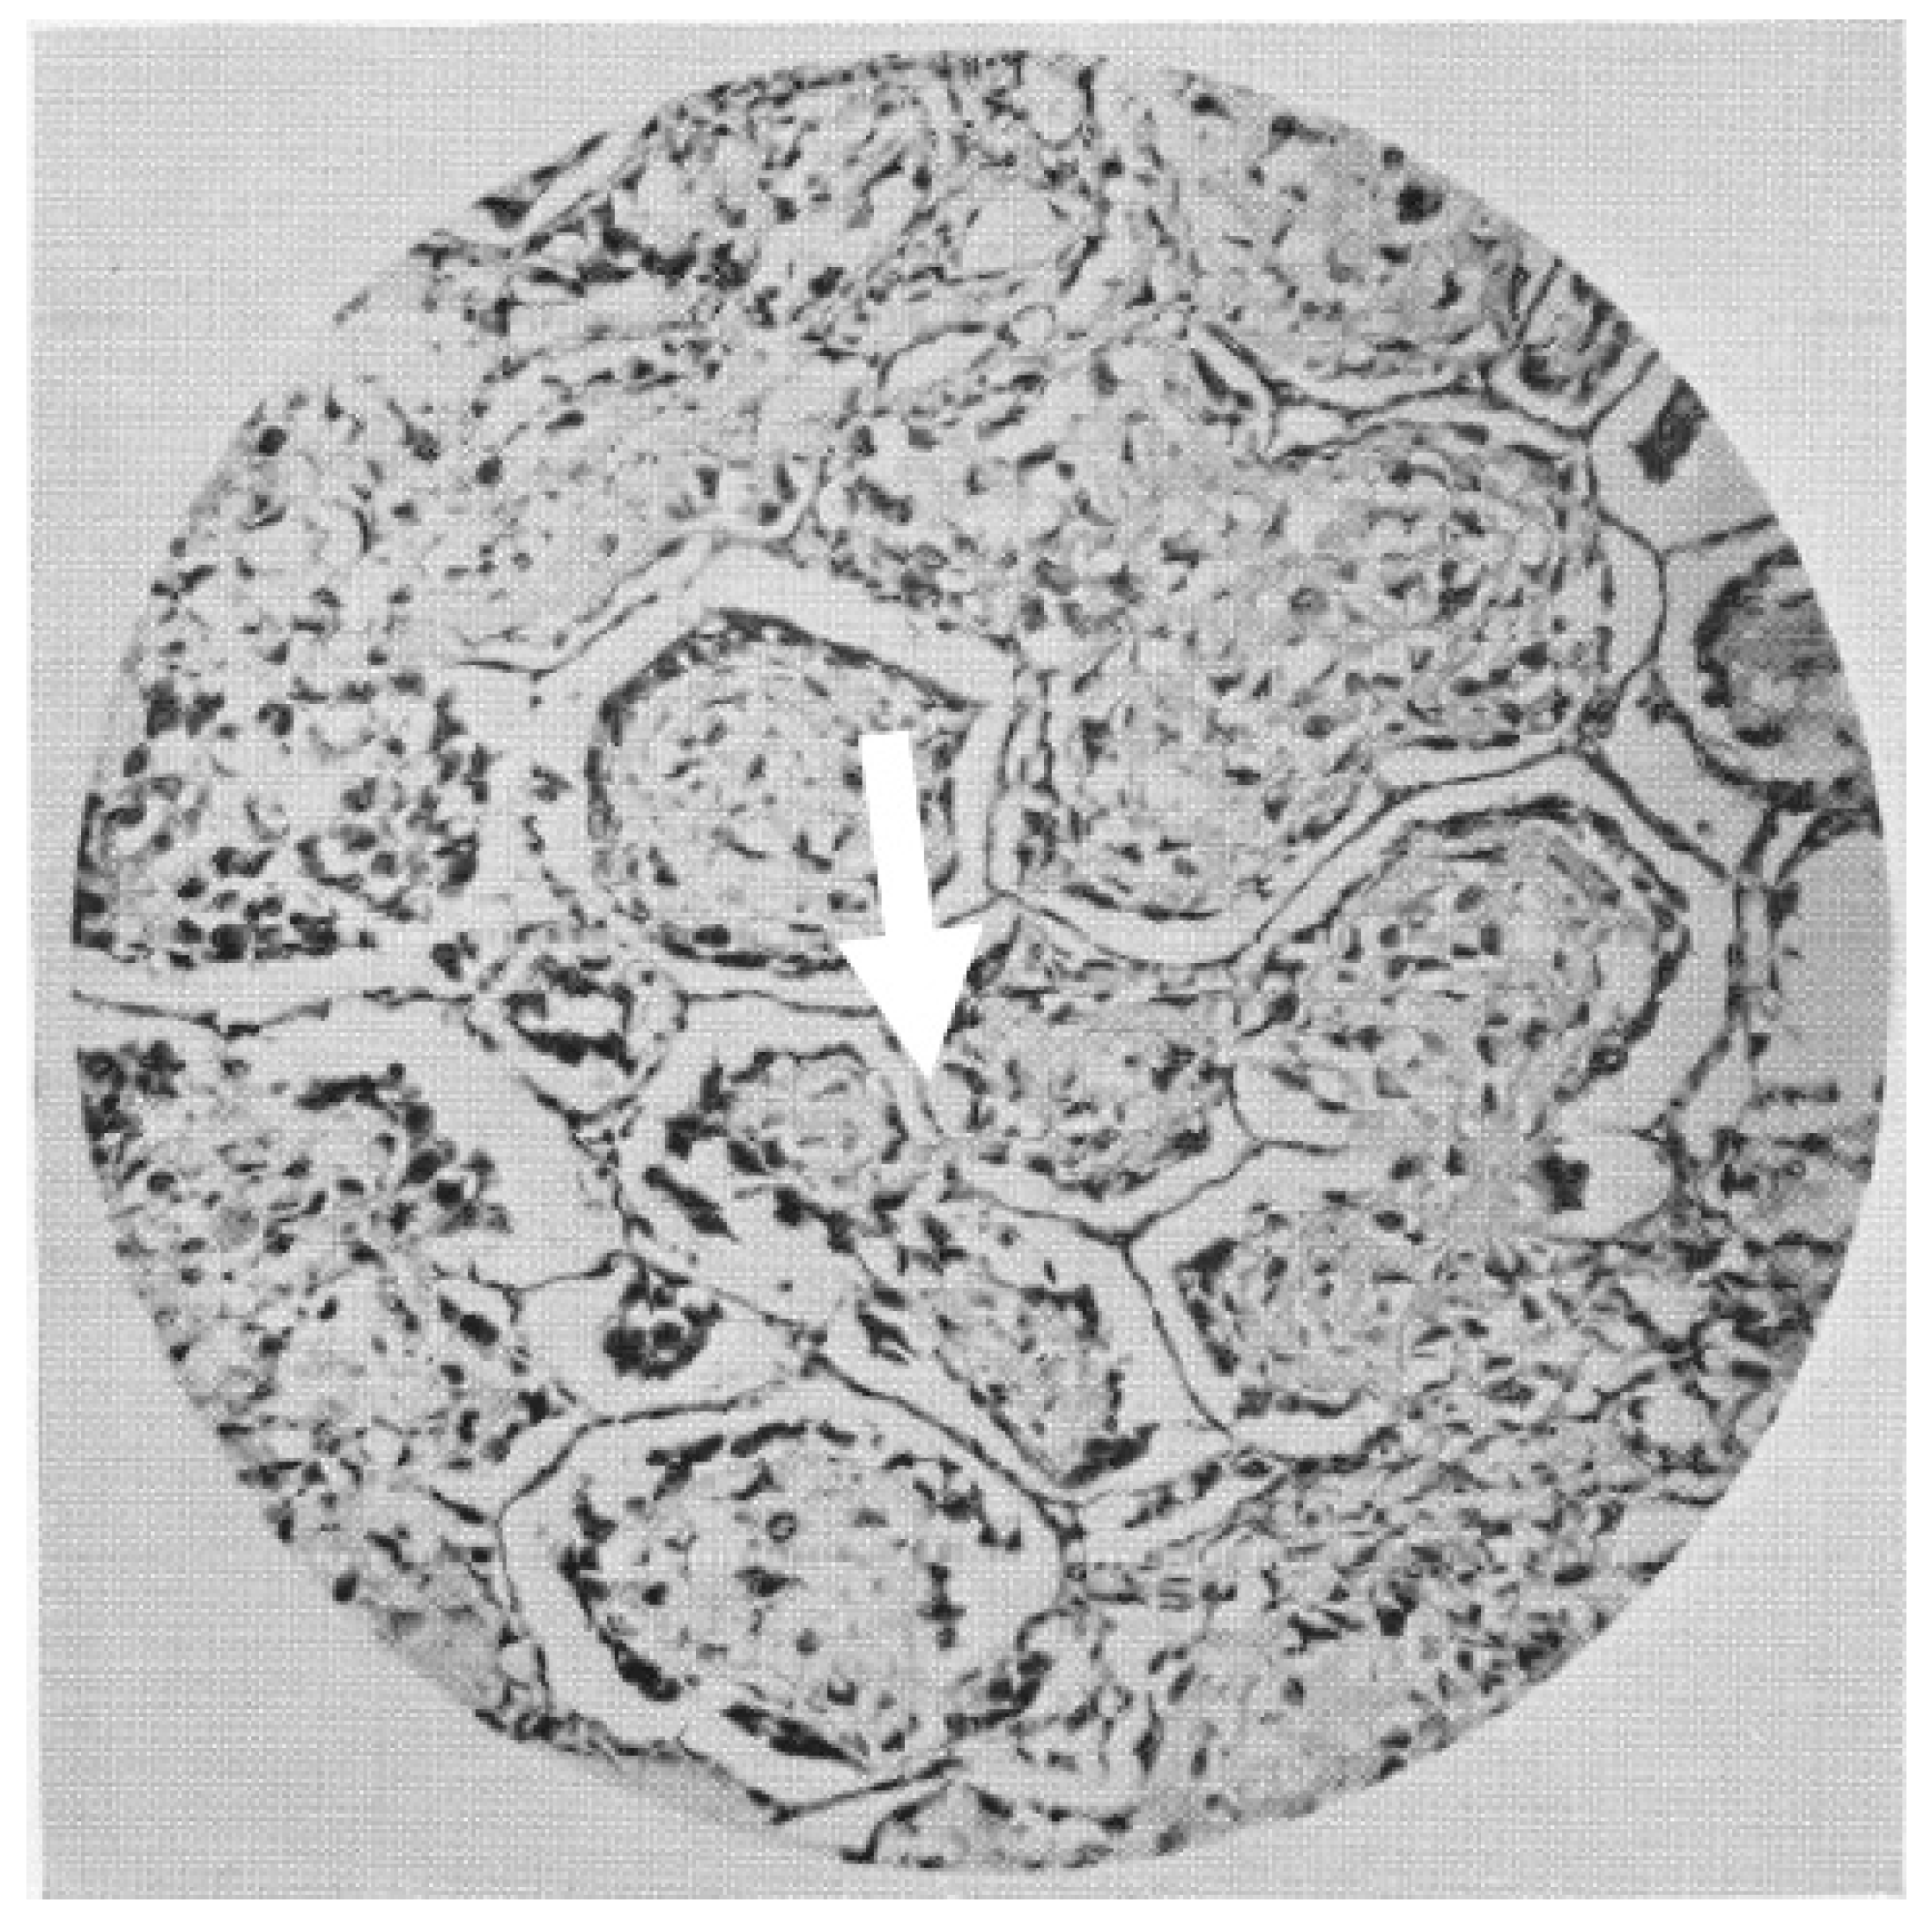

6. Vascular Co-Option

7. Vasculogenic Mimicry